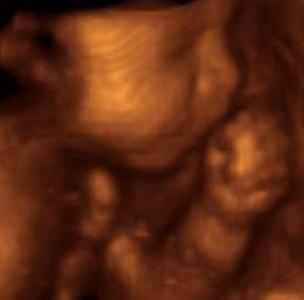

В последнее время 3D-УЗИ предлагают еще более четкое изображение вашего ребенка. Исчезли нечеткие картинки, на которых нужно прищуриться, чтобы различить колено и локоть. Вместо этого вы можете увидеть черты лица вашего ребенка и даже взять домашние фотографии, достойные рамки или альбома для вырезок, чтобы поделиться ими с ребенком позже. Их также иногда называют 4D УЗИ .